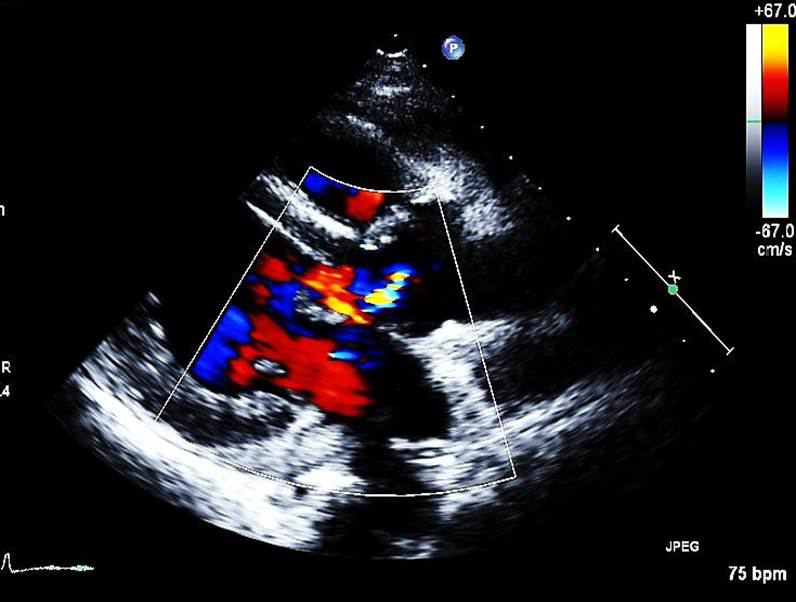

Figure 5: Transthoracic echocardiography after surgery.

Transthoracic echocardiography after repair of ruptured aneurysm shows no residual shunt flow.